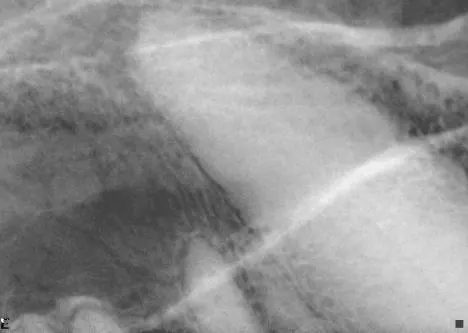

It is less convenient and more technically difficult to obtain high-quality dental images with traditional radiographic techniques. The radiograph machine is usually distant from the dental operatory, making it necessary to move the patient to obtain radiographs. Positioning is more difficult because the tube head is stationary. The need for extraoral film placement increases the difficulty of avoiding overlapping of structures. Dental films placed intraorally can be used with a standard radiographic machine to help with some of these problems; however, the practitioner wishing to incorporate dental radiology into his or her practice is advised to invest in a dedicated dental unit.

Skulls were used for these images. Dental images were obtained with a digital sensor; the traditional radiographs were taken using extraoral technique with a standard radiographic machine.

A radiographic image shows a close-up view of a canine thoracic cavity, highlighting the heart and surrounding structures. The image displays varying densities, indicating the presence of soft tissues and potential abnormalities within the chest area.